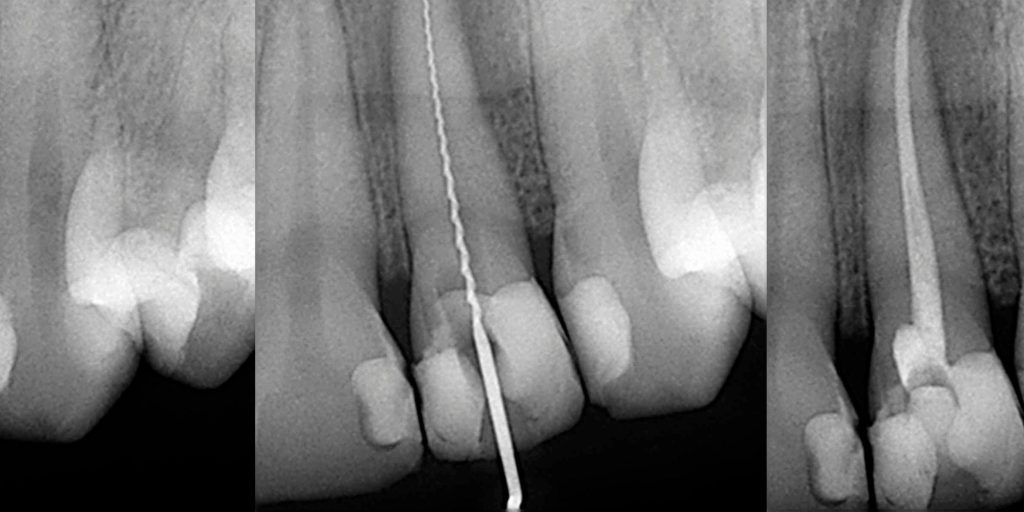

1. معاینه و تصویربرداری: دندانپزشک با رادیوگرافی (X-ray) میزان آسیب را ارزیابی می‌نماید.

5. پر کردن کانال: کانال‌ها با مواد زیست‌سازگار (مانند گوتاپرکا) پر می‌گردند.